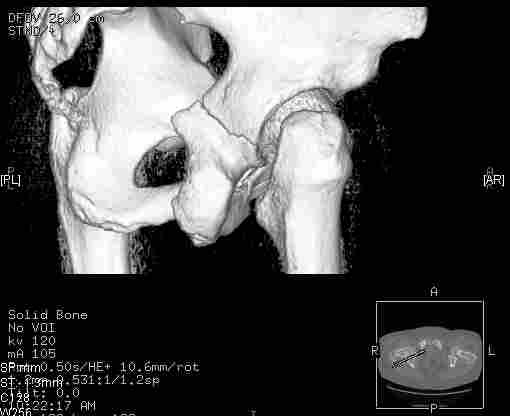

Следом 3d

Приветствую,Антон.Рункова рядом нет,но после полученных данных КТ,обсуждали совместно.Итог обсуждения-развернутый ответ дать не получится,т.к.срезы выбраны не информативные.Если ориентироваться на данные 3D,то ,ИМХО,можно лечить на вытяжении.